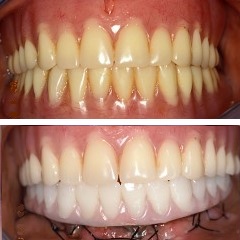

Δείτε επίσης παρακάτω σε φωτογραφίες τα στάδια της τεχνικής καθώς και περιστατικά άμεσης φόρτισης που έχουν θεραπευτεί στο ιατρείο μας σε μια μέρα.

Στάδιο 6:Καινούργια δόντια σε μια μέρα

Αντικατάσταση οδοντοστοιχίας με ακίνητη αποκατάσταση σε εμφυτεύματα σε μία μέρα

Εξαγωγή φυσικών δοντιών και ακίνητη αποκατάσταση σε εμφυτεύματα σε μια μέρα

Άμεση αποκατάσταση άνω και κάτω γνάθου σε μια μέρα